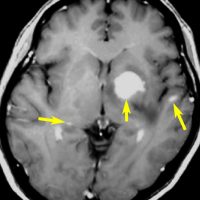

矢印の所を定位脳手術で取りました。病理の結果がリンパ腫と確定されましたから,MTX化学療法をしてから放射線をあてたら,右側のMRIのように腫瘍は消えました。患者さんの症状は良くなって退院したのですがーー。

左から,1回目の再発,2回目の再発,3回目の再発です。再発するたびになんとか治療はできるのですが,違った場所に再発してきてだんだん治療が効かなくなってくることが多いです。このような現象から,脳のリンパ腫は脳に発生するのではなくて,体のどこかに原発巣があるのではないかという考えもあります。もちろん、こんな再発をしないで治ってしまう患者さんも多いです。